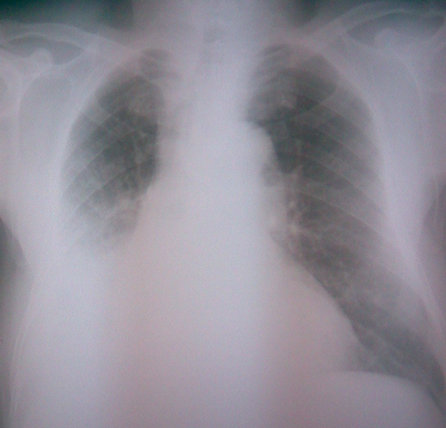

病人男,80岁,咳嗽、胸闷就诊,阴影上缘模糊,仰卧位透视无明显变化

胸廓对称,右下肺密度均匀增高,上缘不清晰,似呈抛物线样改变,左肺野清晰,左膈面光滑,心脏形态大小尚在正常范围。

考虑:1、右侧胸腔中等量积液2、建议ct除外右肺占位性病变

个人认为不太象积液,一个是上缘模糊,二是仰卧位观察基本无改变,膈面、肋膈角仍不可见

有条件的话先做了ct再发报告,首先考虑右下肺感染,积液及占位待排,建议进一步检查。

气管稍向右移,下肺右侧似比左侧窄,卧位立位无变化,实在不像积液。我倒更支持炎症。希望ct释疑

右下肺密度均匀增高,右上肺密度稍高条索状,上缘不清晰,似呈抛物线样改变,纵隔稍向右移,左肺野清晰,左膈面光滑,右肋隔角,左肋隔角锐利。消失心脏形态大小尚在正常范围。

考虑:1、右下肺积浓。2.胸膜肥厚粘连。

右下肺膨胀不全,考虑有占位可能。

胸膜增厚或右下肺不张;